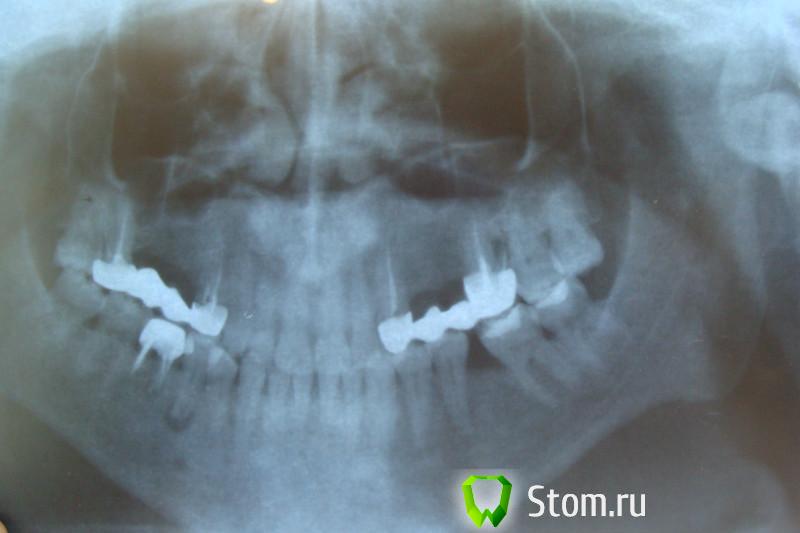

samsonov Опубликовано 15 января, 2012 Поделиться Опубликовано 15 января, 2012 Ну, ладно.Мои 5 копеек.Верите,что у 4.6 обошлось без хирургического вмешательства?Слева- более поздний снимок. Ссылка на комментарий

Kivilgar Опубликовано 15 января, 2012 Поделиться Опубликовано 15 января, 2012 Ну, ладно.Мои 5 копеек.Верите,что у 4.6 обошлось без хирургического вмешательства?Слева- более поздний снимок. Я наверно побоялся бы брать на лечение. Похоже на кисту не связанную с зубом. Вы смелый и удачливый. Ссылка на комментарий